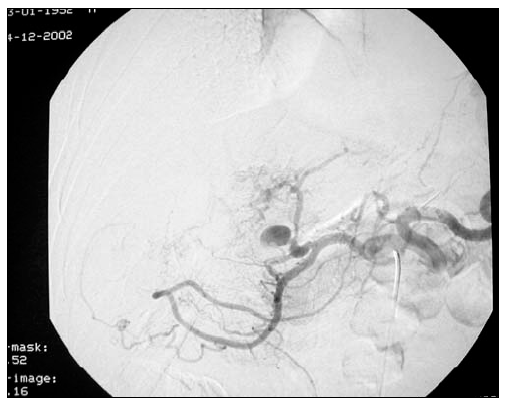

Figure 3. Post-operative cholangiogram showed success of the modified porto-enterostomy.

A different scenario is represented in the case of complex biliary tract injuries when a duct to mucosa anastomosis can not be accomplished. In this setting, we and others [2] have found a Roux-en-Y porto-enterostomy a particularly useful approach. This operation was originally devised in pediatric surgery for the treatment of bilary atresia by Kasai in 1968 [16] and then adopted by general surgery for the treatment of high biliary strictures [17,18]. In our experience, a combination of this procedure with intraoperative stenting of the two major intrahepatic biliary systems with multiple fenestrated semi-rigid stents was a lifesaving procedure in otherwise untreatable high biliary injuries (Figure 3). When feasible, an intrahepatic biliary drain should be placed during preoperative percutaneous cholangiogram and used to guide the portoenterostomy.